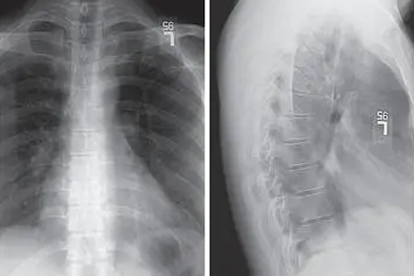

当胸椎黄韧带增厚导致脊髓或神经根严重受压时,手术是必要选择。典型症状包括进行性下肢无力、踩棉花感、大小便功能障碍等。影像学检查若显示椎管狭窄率超过50%,或动态位MRI证实韧带肥厚造成脊髓动态受压,需考虑椎板切除减压术、黄韧带切除术等。术后需配合康复训练预防粘连,如神经松动术、渐进性抗阻运动。合并骨质疏松者还需同步抗骨质疏松治疗,如阿仑膦酸钠维D3片、碳酸钙D3颗粒,以降低邻近节段退变风险。